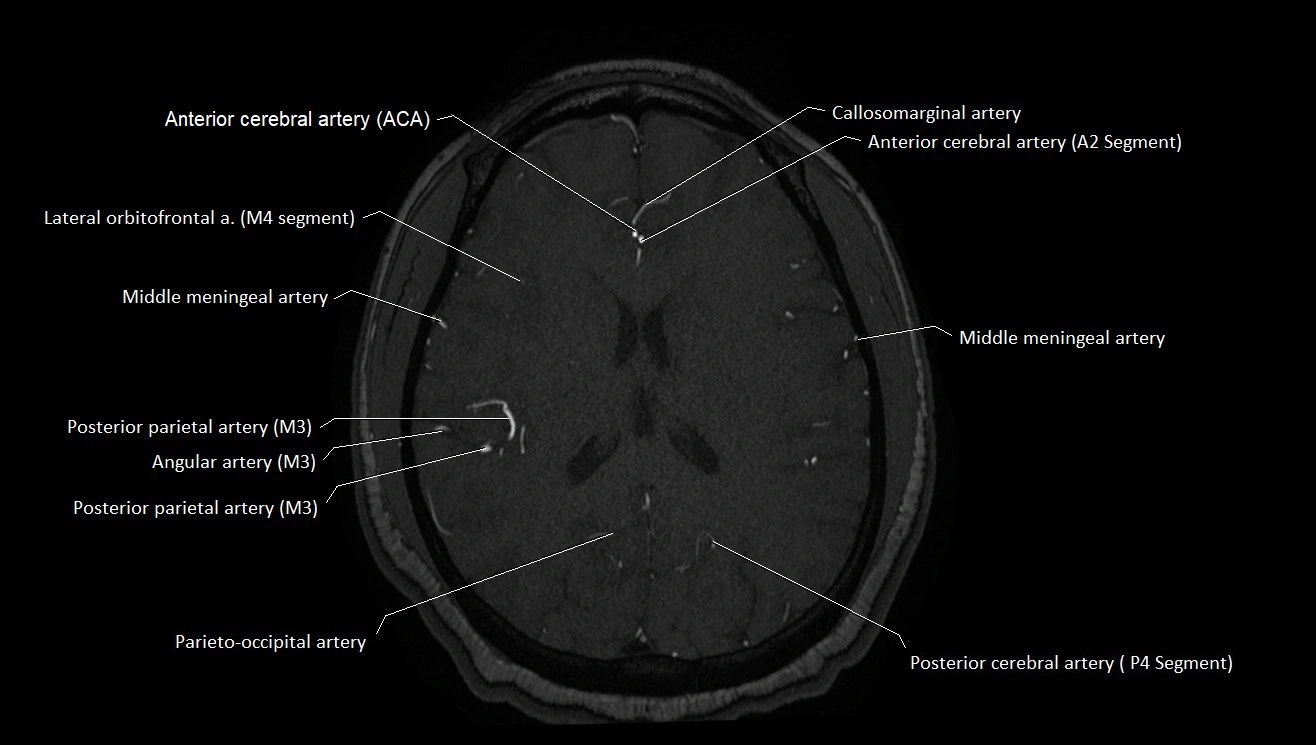

MRA (Magnetic Resonance Angiography):

• Flow-related enhancement makes the AChA appear as a bright, linear vascular signal against suppressed background

• High sensitivity for origin and proximal course; distal branches may be too small to resolve

• Detects stenosis, occlusion, aneurysm, AVM feeders

MRI images

image